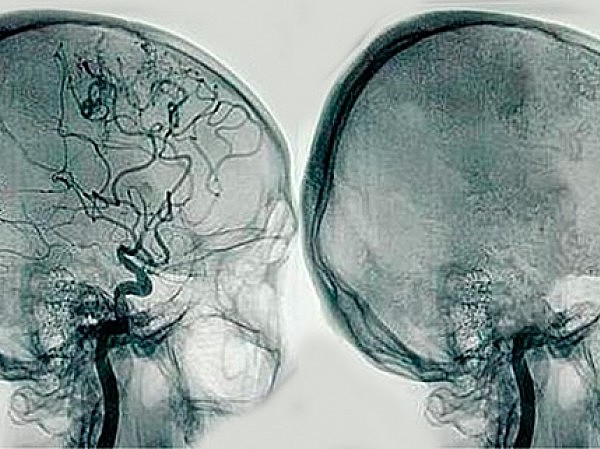

Angiografía

El portugués Egas Moniz fue el primero en el desarrolló la angiografía por contraste como diagnóstico de trastorno celebral. Produciendo imágenes detalladas de los vasos sanguíneos,